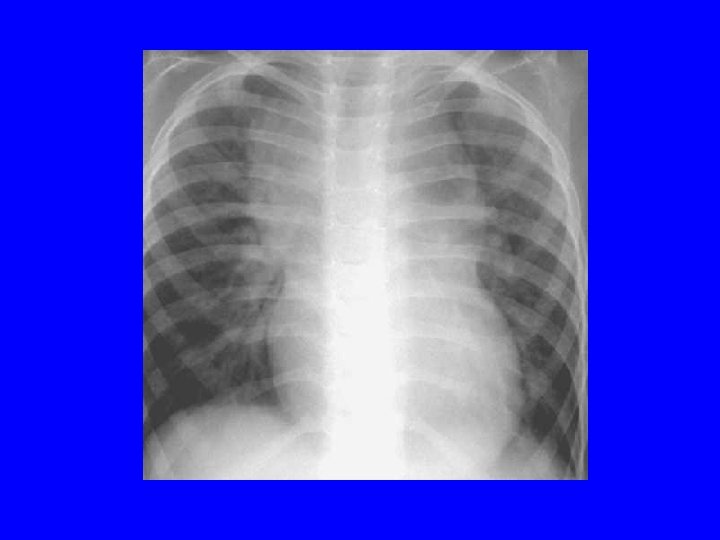

Broncho-Pulmonary Dysplasia • BPD- 36 wk of corrected GA with oxygen requirement • Mechanical trauma (Baro- and Volu-trauma) to susceptible lungs leading to inflammation • Injury is increased in PT due to low levels of antiproteases and antioxidants • Poor compliance, increased WOB, pulmonary hypertension, RVH • Radiographic: honeycomb appearance • Rx- nonspecific as supportive care, inc. calories (120 -150 cal/kg/day), diuretics, bronchodilators, steroids